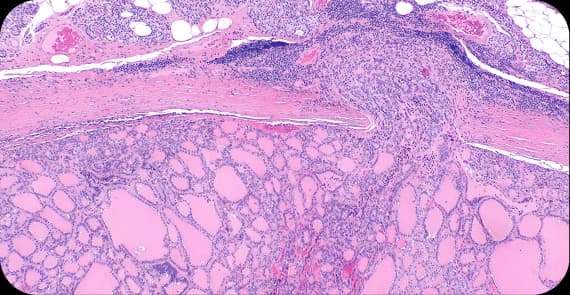

Thyroid cancer stages describe tumour size and spread.

Cancer is confined to the thyroid gland.

This stage involves a larger tumour that remains confined to the thyroid gland.

Spread to nearby lymph nodes or tissues.

Advanced disease with spread to distant organs.

Thyroid cancer stages help determine prognosis and appropriate thyroid cancer treatment.